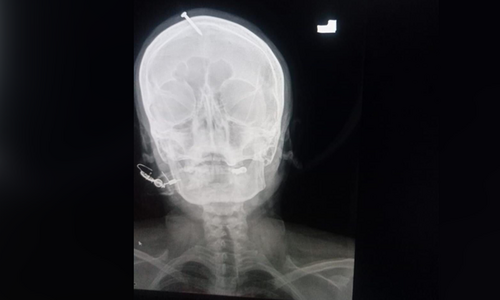

This image shows the X-ray of the victim. — Photo provided by Sirajuddin

The nail was removed from the woman’s head at the Lady Reading Hospital some days ago. The news went viral on social media platforms after it was leaked from the hospital, prompting police to launch an investigation into the matter.

The woman with a bleeding head was brought to LRH few days ago and doctors found a nail hammered into her head. The doctors later removed the nail from the head during a procedure.